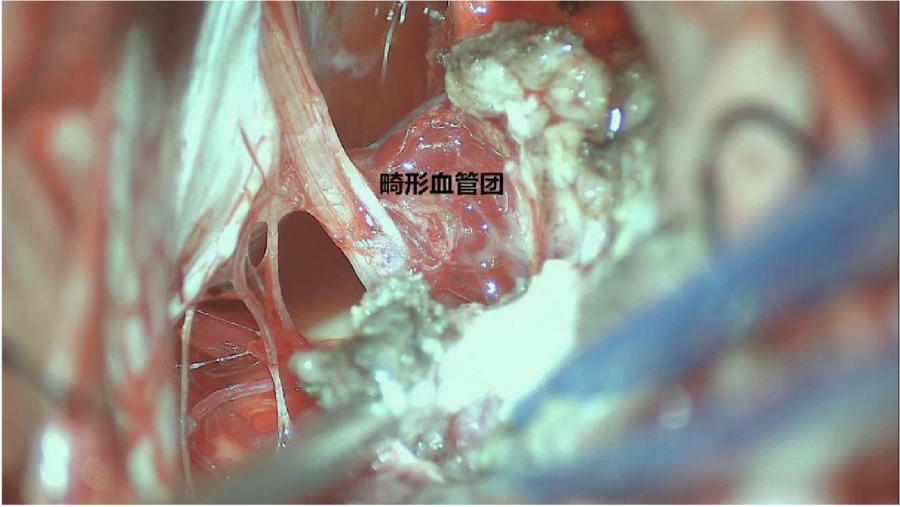

⾏左侧远外侧⼊路脑⼲⾎管畸形切除术,术中所⻅:

3、脑⼲动静脉畸形⼿术切除是注意辨别供⾎动脉与引流静脉,其往往不似其他部位的动静 脉畸形,有叫粗⼤的引流静脉。术中如果不能辨清各⾎管来源与去处,往往会造成不可估量的损失。

4、脑⼲动静脉畸形团周围玩个昂存在复杂的神经及⾎管,操作难度⼤。